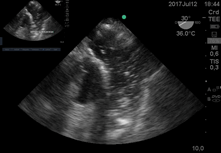

En otra paciente joven durante laparotomía por quiste de ovario presentó PC intaroperatorio luego de arritmia, con ETE se diagnosticó síndrome de Takotsubo.

En las Figuras k se obervan dos pacientes donde se obtuvieron imagenes de 4 cámaras

medioesofágica inmediatamente posterior a reanimación de PC y con fracción de eyección 15% . Uno con distención de aurícula izquierda por Sindrome de Takotsubo el otro de aurícula derecha por McConnell. (Figura k1) y (Figura k 2)